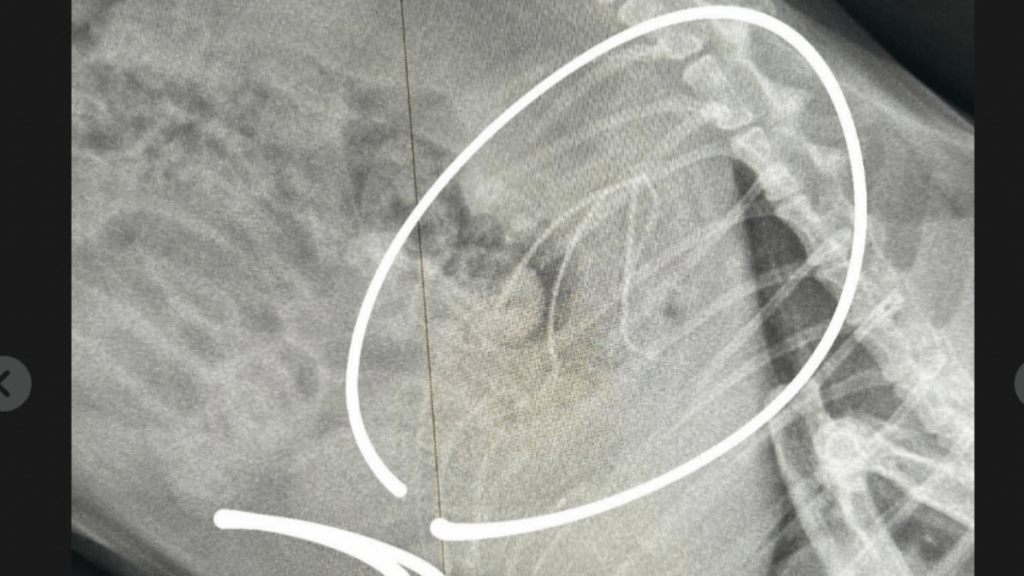

Kediler ve Köpeklerde Yabancı Cisim Yutma

Kediler ve köpekler bazen oyuncak parçaları, ip, plastik veya kemik gibi yabancı cisimleri yutabilir.

Yabancı cisim yutma durumunda görülebilecek belirtiler:

kusma

– iştahsızlık

– karın ağrısı

– halsizlik

– dışkı yapamama

Bu belirtiler görüldüğünde vakit kaybetmeden veteriner kliniğine başvurmak gerekir.

Bazı vakalarda yabancı cisimler endoskopi yöntemiyle ameliyata gerek kalmadan çıkarılabilir.

Kedilerde Yüksekten Düşme Sendromu

Kedilerde özellikle yaz aylarında sık karşılaşılan durumlardan biri yüksekten düşme sendromudur. Bu durum genellikle balkon veya pencerelerden düşme sonucu meydana gelir.

Yüksekten düşme vakalarında şu problemler görülebilir:

– çene kırıkları

– bacak kırıkları

– akciğer travması

– iç kanama